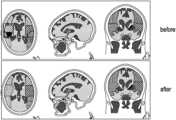

FIG.7 shows slice images of a brain before and after refinement of a segmentation in accordance with an embodiment.

Returning to the embodiment ofFIG.2,FIG.7 shows slice images, from three orthogonal directions, of a brain with boundaries of different M regions determined by segmentation based on non-rigid registration obtained using the embodiment ofFIG.2. Different M regions are indicated using different shading and boundaries are indicated using different line styles. The top three images show segmentations after non-rigid registration but before refinement using the determined planes. The bottom three images show the segmentations after refinement using the determined planes. In the bottom images, it can be seen that some boundaries that were curved before the refinement are now straight. In particular, in the bottom images the boundary lines are straight at boundaries between those M regions where a clinician would expect to see straight or flat boundaries.